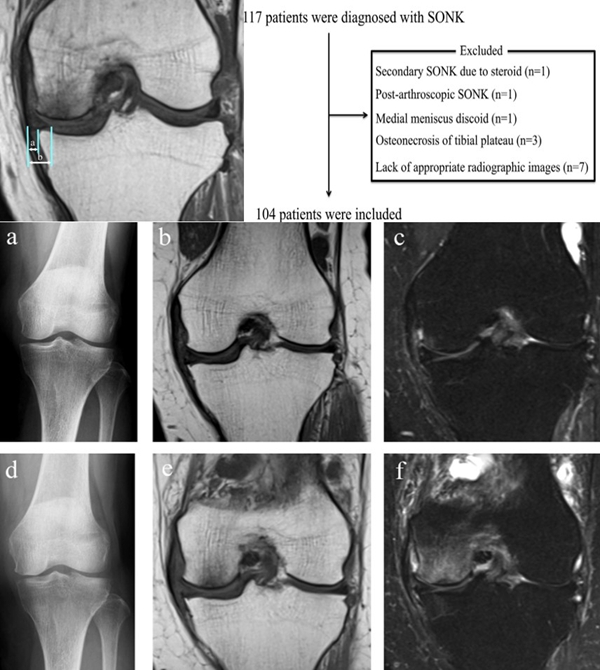

SONK与内侧半月板突出的相关研究中,100%(104)SONK中都有半月板突出,4个SONK在发病前因膝关节疼痛体检发现半月板突出,几个月后通过MRI检查显示存在 SONK。

研究证明半月板挤压是SONK的发病机制之一,半月板挤压的进展可能与SONK的发展有关。

关于影像学评估与SONK的预后的关系,多项研究表明小于3.5cm2的小坏死病变可进行保守治疗,在冠状位X片上5cm2软骨下病变面积作为预测预后不良和高风险进展的临界值,前后位X片坏死区>50%髁,会迅速塌陷,病变范围很大(>40%髁/前后位X 片)或有早期骨关节炎的影像表现,保守欠佳。

早期(3月内)内侧半月板相对挤压百分比≥33%,是SONK发病1年后预后不良的预测指标,MRI检查没有局灶性轮廓塌陷和髁深处没有低信号线(隔离带),预后好,股胫角>180°(下肢力线内翻>6°)和MRI上深度>20mm 预示SONK患者症状发作后1年预后不良。

内侧半月板挤压(MME)以绝对值和挤压相对百分比 (RPE) 的形式呈现,其定义为挤压半月板宽度与整个半月板宽度相比的百分比